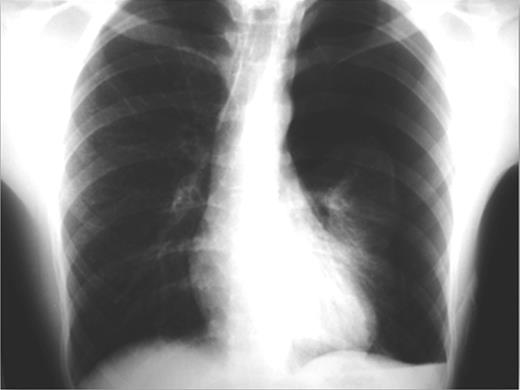

An otherwise-healthy, non-smoker, 20-year-old, overweight (BMI 29.8 kg/m2) Greek male patient was presented to the emergency department complaining of low-intensity chest pain and breathlessness of progressive worsening over the preceding 7 days. On admission, physical examination revealed diminished breath sounds on both sides. Blood pressure was 125/70 mmHg, heart rate 100 beats/min, SaO2 97% on air and axillary temperature 36.8°C. Laboratory tests were normal. Initial plain chest X-ray demonstrated bilateral pneumothoraces (more prominent on the left side) and no deviation of the trachea (Fig. 1).

Plain chest X-rays on admission revealing bilateral pneumothorax.